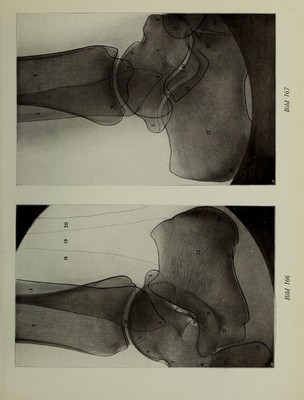

Atlas typischer Röntgenbilder vom normalen Menschen : ausgewählt und erklärt nach chirurgisch-praktischen Gesichtspunkten, mit Berücksichtigung der Varietäten und Fehlerquellen, sowie der Aufnahmetechnik / von Rudolf Grashey.

Credit: Atlas typischer Röntgenbilder vom normalen Menschen : ausgewählt und erklärt nach chirurgisch-praktischen Gesichtspunkten, mit Berücksichtigung der Varietäten und Fehlerquellen, sowie der Aufnahmetechnik / von Rudolf Grashey. Source: Wellcome Collection.